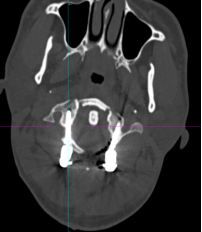

术中“O”-臂机导航图像

在麻醉手术科的配合下,有了高精尖的第二代“O”-臂机的辅助,加之姜主任丰富的临床经验,手术非常顺利。第二代“O”-臂机扫描颈椎三维重建显示寰椎移位的骨块复位完成,寰枢椎椎弓根螺钉位置良好。术后,患者颈部疼痛症状明显改善。